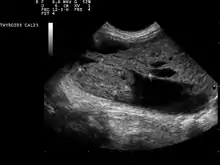

| Ultrasound artifacts showing a "comet tail" from a colloid nodule indicate a benign nodule | |

Ultrasound imaging is useful as the first-line, non-invasive investigation in determining the size, texture, position, and vascularity of a nodule, accessing lymph nodes metastasis in the neck, and for guiding fine needle aspiration cytology (FNAC) or biopsy. Ultrasonographic findings will also guide the indication to biopsy and the long term follow-up.[10] High frequency transducer (7–12 MHz) is used to scan the thyroid nodule, while taking cross-sectional and longitudinal sections during scan. Suspicious findings in a nodule are hypoechoic, ill-defined margins, absence of peripheral halo or irregular margin, fine, punctate microcalcifications, presence of solid nodule, high levels of irregular blood flow within the nodule[11] or "taller-than-wide sign" (anterior-posterior diameter is greater than transverse diameter of a nodule). Features of benign lesion are: hyperechoic, having coarse, dysmorphic or curvilinear calcifications, comet tail artifact (reflection of a highly calcified object), absence of blood flow in the nodule, and presence of cystic (fluid-filled) nodule. However, the presence of solitary or multiple nodules is not a good predictor of malignancy. Malignancy is only diagnosed when ultrasound findings and FNAC report are suggestive of malignancy.[11] The TI-RADS (Thyroid Imaging Reporting and Data Systems) are sonographic classification systems which describe the suspicious findings of thyroid nodules.[12] It was first proposed by Horvath et al.,[13] based on the BI-RADS (Breast Imaging Reporting and Data System) concept. Several systems were subsequently proposed and adopted by international scientific societies. Their main aims are to characterize the risk of malignancy of nodules to better select nodules to submit to fine-needle aspiration cytology.[14] Another imaging modality, which is ultrasound elastography, is also useful in diagnosing thyroid malignancy especially for follicular thyroid cancer. However, it is limited by the presence of adequate amount of normal tissue around the lesion, calcified shell around a nodule, cystic nodules, coalescent nodules.[15]